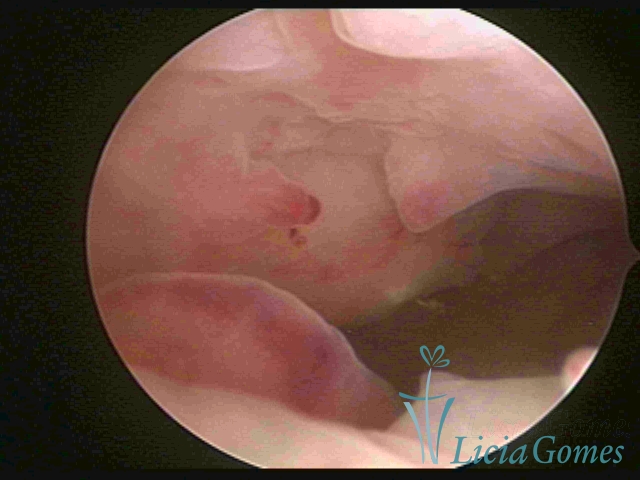

A Hiperplasia Complexa tem um aspecto pseudo polipoide, lembrando tecido cerebroide ou com reação deciduoide. A vascularização superficial é mais evidente e com vasos em formatos de saca-rolha ou espirais.

A Hiperplasia atipia e o aspecto histeroscópico são semelhantes à da hipertrofia complexa, visualizando também a vascularização com atipias. Com o aumento do calibre dos vasos superficiais, pode ser encontrado também tecido em necrose.